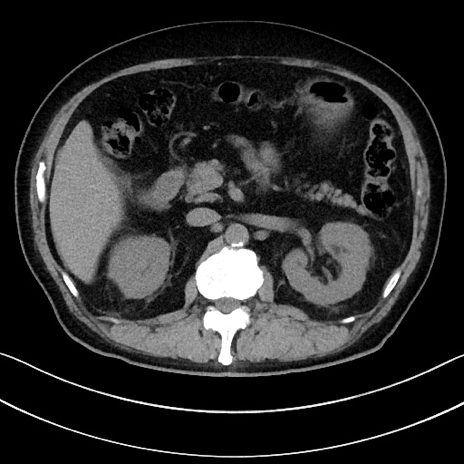

症例15(横断像)

【症例】70歳代男性

【主訴】腹痛

【現病歴】今朝から腹痛あり。全体的に痛い。特に左上の方。排ガスが今日はない。冷や汗が出る。

【既往歴】直腸癌術後

【身体所見】左側腹部〜上腹部に圧痛あり。腹膜刺激症状明らかなではない。軽度反跳痛。左下腹部に術後瘢痕あり。

【データ】WBC 7700、CRP 0.02